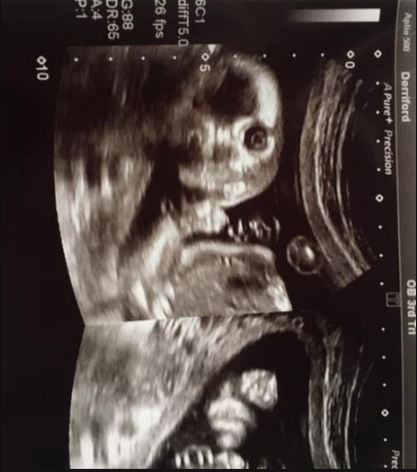

17/02/2020 16:00Đi siêu âm, bà mẹ bất ngờ khi thấy con đang 'nhìn chằm chằm' vào mình

Mới đây, cô Jo Greer, 34 tuổi (sống tại Plymouth - Anh) cũng đã có kỉ niệm khó quên khi đi siêu âm thai ở tuần 20. Hình ảnh siêu âm cho thấy em bé trong bụng như đang mở to mắt và nhìn chằm chằm vào người đối diện đã khiến cô Jo Greer bật cười: "Tôi nghĩ mọi người chưa nhìn thấy bức ảnh nào như này. Nhiều người còn nhấn like tấm ảnh và nhắn tin cho tôi nữa".

Nữ hộ sinh ở bệnh viện cho biết điều này không hay xảy ra khi siêu âm thai: "Lúc đầu khi siêu âm thì mọi chuyện vẫn bình thường, nhưng sau đó em bé đột nhiên quay mặt nhìn thẳng vào ống kính, điều này khá hiếm gặp nhưng cũng rất thú vị".

Cô Jo cũng dự định sẽ tặng lại cho con mình bức ảnh độc đáo này vào sinh nhật 18 tuổi của bé.